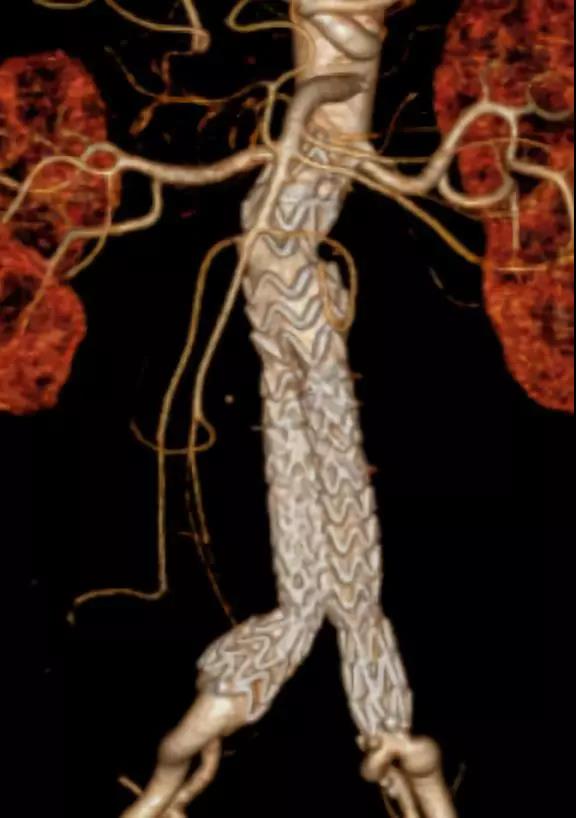

此次研究,纳入腹主动脉瘤的最大直径为85mm,平均直径为50.78mm;最短瘤颈长度为11mm,平均长度为31.34mm;最大肾下成角为74.6度,平均角度为32.48度。从动脉瘤最大直径变化来看,经过腹主动脉腔内治疗后,在出院前和术后6个月都有所减小。 在此次研究中,先健Yuranos™新一代腹主动脉覆膜支架系统临床试验初步展现了优秀的临床试验结果,其30天内MAE发生率低,安全性得以验证;而且由于该产品的柔顺性有较大提升,输送器直径减小,对于短瘤颈和角度大的病例是更好的选择。 入组病例展示: 病例一:男性,年龄69岁,既往高血压,糖尿病病史。术前腹主动脉瘤直径67.3mm,近端瘤颈长度23.2mm,近端锚定区直径21.2mm,肾下成角60.5度。 术中从右侧股动脉穿刺,选用先健型号为AB-2412-50-120的主体支架,支架近端定位于右肾动脉开口处,后释放打开裸支架,并向下释放主体短分支,左侧输送进入先健髂动脉延长支架IE-1416-100,并释放,保留左侧髂内动脉。接着释放主体长分支,右侧输送进入先健髂动脉延长支架IE-1424-80,并释放,保留右侧髂内动脉。 手术顺利,无内漏,持续时间1小时10分钟。术后CTA检查,支架形态良好,无内漏。详见下图: 术前影像 术中影像 出院前影像 术后6个月影像 术后1年影像 病例二:女性,年龄72岁,既往高血压,静脉曲张病史。术前腹主动脉瘤直径48.81mm,近端瘤颈长度16.15mm,近端锚定区直径18.43mm,肾下成角66度。 术中从右侧股动脉穿刺,选用先健型号为AB-2412-50-140的主体支架,支架近端定位于右肾动脉开口处,后释放打开裸支架,并向下释放主体短分支,左侧输送进入先健髂动脉延长支架IE-1414-120,并释放,保留左侧髂内动脉。接着释放主体长分支,右侧输送进入先健髂动脉延长支架IE-1414-80,并释放,保留右侧髂内动脉。